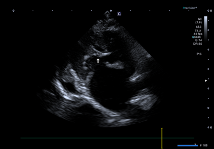

실제 혈전 확인

실제로 초음파 검사 중 대동맥 분지부(aortic bifurcation) 바로 앞쪽에서 컬러 도플러 상 혈류가 끊긴 부분이 관찰되었으며, 이는 다량의 혈전이 혈관을 막고 있는 소견이었습니다.

환자의 초음파사진(혈전이 혈관을 막고 있는 사진)/ 출처: 24시동탄리더스동물의료원

결과적으로 동맥혈전색전증 (ATE, 흔히 saddle thrombus) 이 확인되었고, 이로 인해 양측 후지 마비 증상이 발생한 것으로 판단되었습니다.